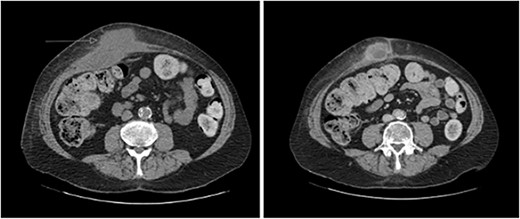

A 65-year-old gentleman with a body mass index of 29.6 and medical history of Guillain–Barré syndrome, type 2 diabetes mellitus, hypertension, and chronic pain was referred to our outpatient clinic with intermittent upper abdominal pain. His surgical history included an open appendicectomy. He was wheelchair-bound outside his home and received weekly assistance from a carer. On examination he was anicteric. His abdomen was soft, but a mildly tender mass was palpable in the right upper quadrant. An initial computed tomography (CT) scan showed thickening of the gallbladder and a collection extending from the fundus and infiltrating the anterior abdominal wall (Fig. 1). Further scans showed extension of the collection towards the midline (Fig. 2). He subsequently presented to the emergency department with purulent discharge from an external orifice adjacent to the umbilicus. An ultrasound-guided 6Fr pigtail drain was then placed into the known abdominal wall collection.

CT abdomen with portal venous contrast showing gallbladder collection extending to lateral abdominal wall.